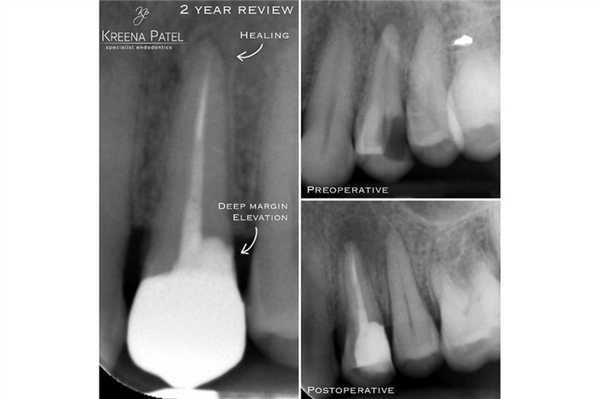

Концепция «deep margin elevation» (поднятие уровня глубокого края дефекта) впервые была предложена Dietschi and Spreafico в 1998 году. Но приобрела она значительную популярность после работ Pascal Magne и Roberto Spreafico «Deep margin elevation: a paradigm shift» в 2012 году.

Что такое поднятие уровня глубокого края дефекта (deep margin elevation - DME)?

DME - это, по сути, прямая реставрация, которая позволяет поднять край дефекта до уровня десны или даже выше ее уровня.

Непрямые реставрации с адгезивным механизмом фиксации являются довольно частым выбором врачей-стоматологов, учитывая их эстетичность и консервативность. Данный тип реставраций также способствует сохранению большего объема тканей зуба. Однако при фиксации подобных конструкций необходимо контролировать уровень влажности рабочего поля, дабы не компрометировать силу бондинговой связи. Удаление излишков композитного цемента часто может вызвать кровотечение с поддесневой области, и таким образом нарушить весь адгезивный протокол. В долгосрочной перспективе такие последствия ассоциированы с эффектом микроподтекания и расцементировки коронки. DME может помочь решить подобные проблемы и оптимизирует условия для фиксации коффердама (фото 1).

Фото 1. Повторное эндодонтическое лечение и фиксация E.max накладки на зуб LR6 a) Рентгенограмма до ревизии канала. b) Повторное лечение корневого канала и формирование композитной культи. Пациент был направлен к своему лечащему стоматологу для выполнения реставрации с перекрытием бугров. с) Препарирование под накладку; дистальный край сформирован на композитной основе. d) Изоляция коффердама перед фиксацией. e) Изолирование соседних зубов при помощи тефлоновой ленты. f) Фиксация накладки на композитный цемент. g) Очистка излишков цемента. h) Вид после фиксации.

DME менее важен при использовании традиционных цементов (цинк-фосфатных или СИЦ) для фиксации непрямых реставраций. Данные материалы мене чувствительные к промахам изоляции, а их излишки могут быть удалены после полной полимеризации. Однако в подобных случаях достаточно сложно получить качественный оттиск (фото 2).

Фото 2. Лечение корневых каналов и формирование композитной культи на зубе LL6. Пациент был направлен к лечащему врачу для изготовления накладки с перекрытием бугров. Золотая накладка была зацементирована на Fuji Plus. Дистальный край находился под десной, а край накладки был сформирован на композитной реставрации (DME). Граница препарирования на всех поверхностях находилась в границах тканей зуба, кроме дистальной поверхности. Рентгенограмма, полученная через год, демонстрирует признаки заживления периапикального поражения.